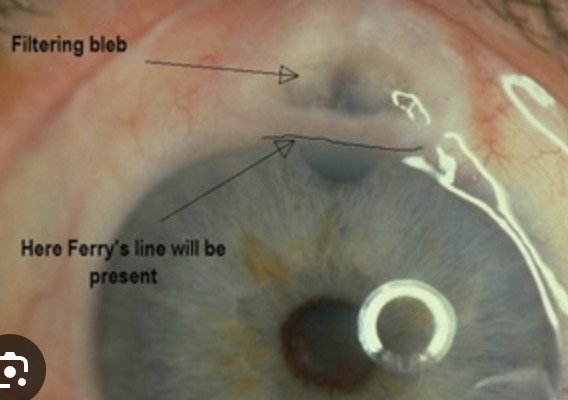

Ferrys line - filter bleb

Dellen: corneal thinning at lumbus with adjacent corneal or connj elevation. Results in poor tear speading → stromal dehydaration. Adjacent to heme, bleb, pterygium, tumor, strab surgery.

Plan: Lubricating drops or ointment AM and PM. Treat causative lesion. RTC 7 days